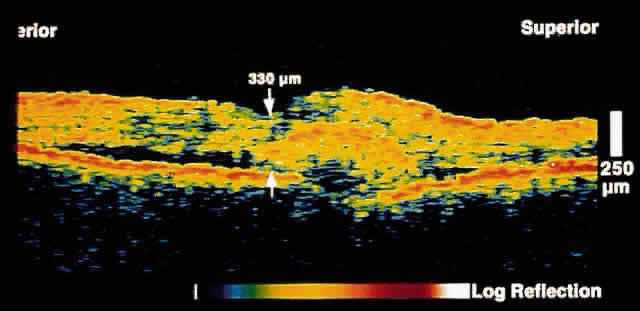

Fig. 3. Several weeks later, an OCT taken through the same area reveals partial

resolution of the neurosensory detachment. Fig. 3. Several weeks later, an OCT taken through the same area reveals partial

resolution of the neurosensory detachment.